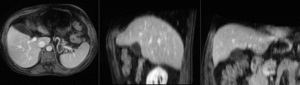

this is a pre-op CT + contrast reference image. All images are aligned into this space lleft this is the pre-op MRI we seek to align with the CT

fixed image/target moving image

Input Data

• reference/fixed : pr-op CT, 0.95 x 0.95 x 5 mm voxel size

• moving: intra-op MRI, 0.78 x 0.78 x 2.5 mm axial,

unregistered MRI & CT